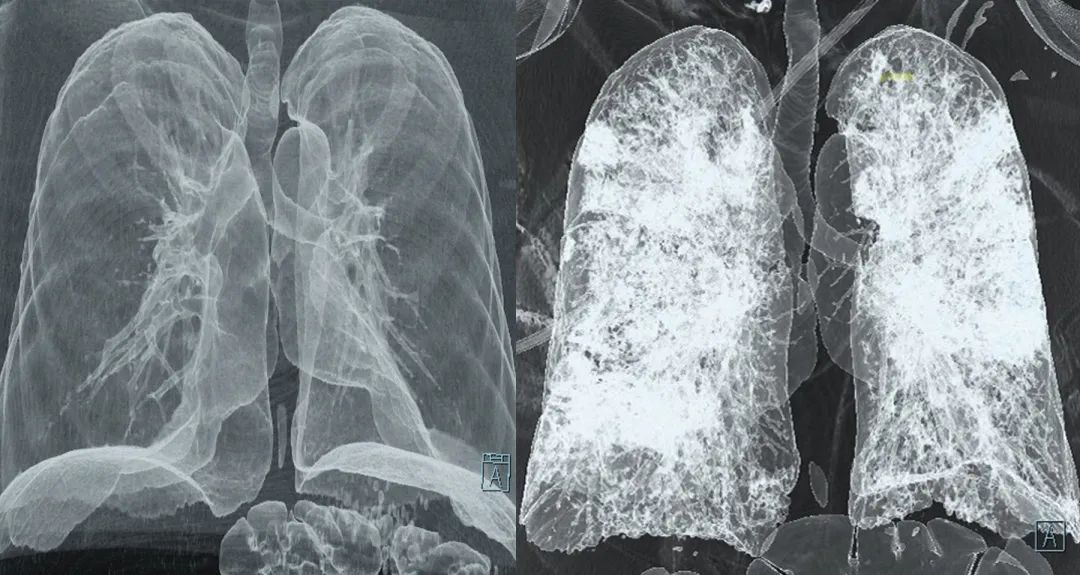

纤维化是一种病理过程,涉及器官或组织内纤维结缔组织的过度增生和沉积。这通常发生在损伤或炎症的修复过程中,但如果修复反应过度或失控,就会导致纤维化的发生。纤维化可以影响多个器官,如肝脏、肺、肾脏等,导致器官功能减退甚至衰竭。